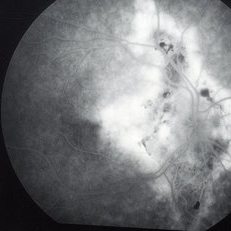

Histoplasmosis and Subfoveal Neovascular Membrane

Histoplasmosis and Subfoveal Neovascular Membrane

Mar 27 2019 by Gary R. Cook, MD, FACS

Late-phase fluorescein angiogram image of the right eye of a 59-year-old white male with ocular histoplasmosis and a subfoveal neovascular membrane showing late leakage and diffusion of dye from the membrane; V.A.= 20/80+2.

Imaging device: Topcon VT-50

Condition/keywords: FA late phase, fluorescein angiogram (FA), ocular histoplasmosis syndrome (OHS), peripapillary atrophy, presumed ocular histoplasmosis syndrome (POHS), subfoveal neovascular membrane